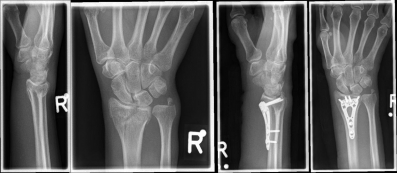

Pictures: A distal radius fracture with joint involvement (C-fracture) was treated with a plate osteosynthesis. After surgery, the plaster can be removed and physiotherapy exercises can be performed.

Complicated fractures involving the articular surface or dislocation should be surgically treated. Open fractures in which the skin is injured and bone is exposed require immediate surgical care. An involvement of the articular surface can lead to a restriction of the mobility in the wrist and therefore requires an anatomically exact reduction. The standard procedure for distal radius fractures is the provision of a titanium plate applied by the diffraction-side (palmar plate osteosynthesis) or the application of an external holder (external fixator).

Pictures: In this case, the articular surface of the wrist was completely destroyed, so that only a therapy by means of outer retainer and some K-wires to correct the position was possible. Here is a practice only after removal of the outer holder after 6-8 weeks possible. Such severe joint injuries often lead to premature joint wear